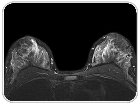

بررسی میزان پاسخ بیمار به شیمی‌درمانی سرطان پستان با استفاده از MRI

۹ خرداد ۱۳۹۱

در بررسی‌های جدید مشخص شده است که استفاده از تصویربرداری رزونانس مغناطیسی (MRI) به‌منظور بررسی اثر شیمی‌درمانی بر سرطان پستان بسیار دقیق‌تر از ارزیابی‌های بالینی است، که این امر برای شیمی‌درمانی قبل از جراحی بسیار کمک‌کننده است. ادامه>>